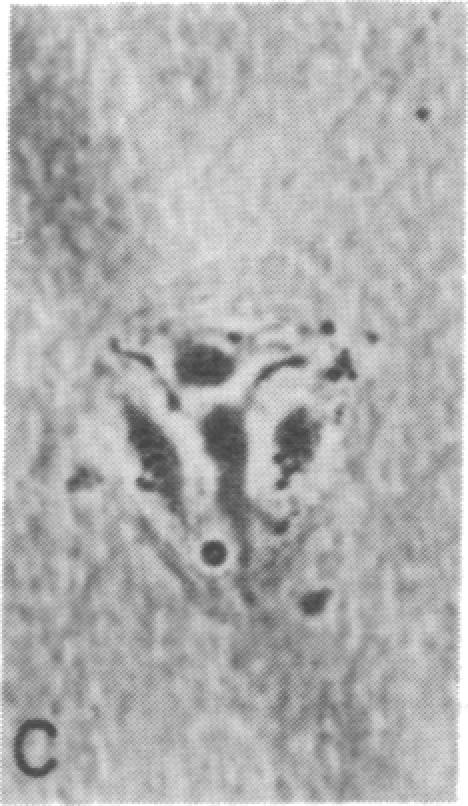

Capillary endothelial cells from rats, calves, and humans, have been carried in long-term culture. Bovine capillary endothelial cells have been cloned and maintained by serial passage for longer than 8 months. This prolonged culture was accomplished by using tumor-conditioned medium, gelatin-coated plates, and a method of enriching cells in primary culture. Cultured bovine capillary endothelial cells produce Factor VIII antigen and angiotensin-converting enzyme, but do not have Weibel-Palade bodies. Human cells do contain Weibel-Palade bodies. Capillary endothelial cells are distinguished from aortic endothelial cells by their requirement for conditioned medium. Bovine capillary endothelial cells in regular medium grow slowly with a mean doubling time of 67 hr and eventually die. In tumor-conditioned medium, these cells grow rapidly with a doubling time of 28 hr and continue to proliferate for as long as the tumor-conditioned medium is present. In contrast, bovine aortic endothelial cells grow as rapidly in regular medium as in tumor-conditioned medium. This method allows the production of pure capillary endothelial cells that may prove useful for studies of tumor angiogenesis, metastatic mechanisms, and the role of capillary endothelium in other pathologic states.

大鼠、小牛和人类的毛细血管内皮细胞已进行长期培养。牛毛细血管内皮细胞已被克隆,并通过连续传代维持了8个月以上。这种长期培养是通过使用肿瘤条件培养基、明胶包被的培养板以及一种在原代培养中富集细胞的方法来实现的。培养的牛毛细血管内皮细胞产生因子VIII抗原和血管紧张素转换酶,但没有魏贝尔-帕拉德小体。人类细胞确实含有魏贝尔-帕拉德小体。毛细血管内皮细胞与主动脉内皮细胞的区别在于它们对条件培养基的需求。在常规培养基中,牛毛细血管内皮细胞生长缓慢,平均倍增时间为67小时,最终死亡。在肿瘤条件培养基中,这些细胞生长迅速,倍增时间为28小时,只要有肿瘤条件培养基存在,就会继续增殖。相比之下,牛主动脉内皮细胞在常规培养基中和在肿瘤条件培养基中生长速度一样快。这种方法可以产生纯的毛细血管内皮细胞,这可能对肿瘤血管生成、转移机制以及毛细血管内皮在其他病理状态中的作用的研究有用。